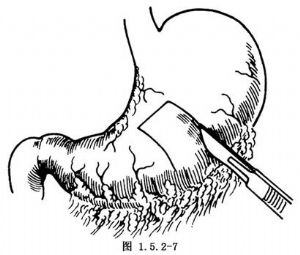

这是常用的一种永久性胃造口术。进腹后显露出胃前壁,于胃前壁中部设计一个长约7cm、宽5cm长方形的瓣。瓣的底部位于胃大弯侧使做成的胃壁管道容易拖出腹壁切口。于其远近两侧各上一把肠钳夹住胃壁暂时夹闭胃腔以防止胃内容物外流并减少出血。按设计将胃壁做Π形的全层切开(图1.5.2-7)。胃黏膜下血管应逐一缝扎止血,吸净胃内容物,用两把Allis钳夹住胃瓣小弯侧的两个角,将胃瓣向大弯侧翻开(图1.5.2-8)。用一根F14~16号导尿管置入胃腔约7~8cm,导管置于翻开的胃瓣中央。自小弯侧开始缝合胃壁切口,用细的不吸收线做全层间断缝合。缝至胃瓣的基底部时,继续缝合胃瓣的两边直至瓣端将导管包住,使成一胃瓣管,然后再加一层不吸收线Lembert缝合。导管仍留在胃瓣管内(图1.5.2-9)。将胃瓣管经腹壁切口上端或另做一切口拖出,应超过皮肤表面1cm,再用细的不吸收线将胃瓣管的浆肌层与腹膜切口四周做固定缝合,将露出皮肤切口以外的胃瓣管口的黏膜与皮肤切口固定缝合(图1.5.2-10)。